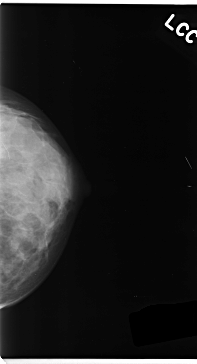

C_0152_1.LEFT_CC

LEFT_CC LINES 4720 PIXELS_PER_LINE 2552 BITS_PER_PIXEL 12 RESOLUTION 50 NON_OVERLAY

LESION_TYPE MASS SHAPE LOBULATED MARGINS ILL_DEFINED

ASSESSMENT 5

SUBTLETY 3

PATHOLOGY MALIGNANT